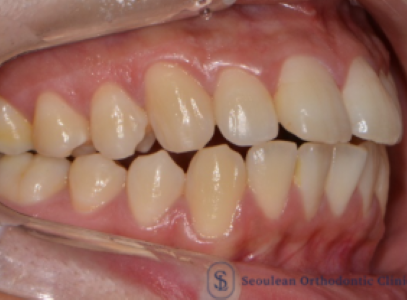

분당 판교 교정치과|10대 여학생 심한 덧니·중심선 편위, 선천적 결손치 발치교정 치료 사례